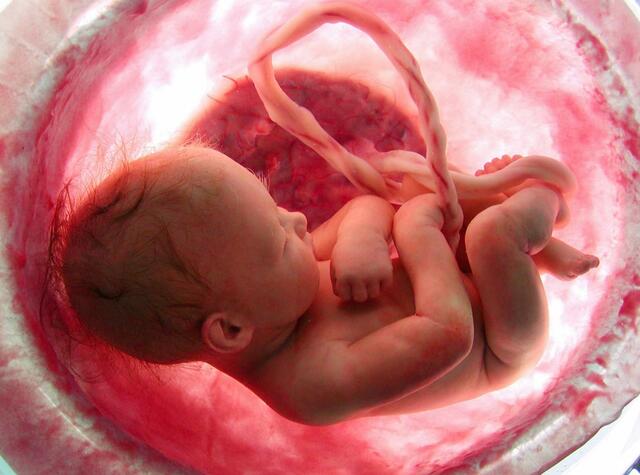

• Period: 63 to 280

Periodo de feto

Se trata de la tercera y última fase del periodo prenatal, que abarca desde la novena semana hasta el momento del parto

• Desarrollo de órganos completo

280

Desarrollo de órganos completo

Durante el ultimo trimestre el bebé ya tiene los órganos necesarios para sobrevivir